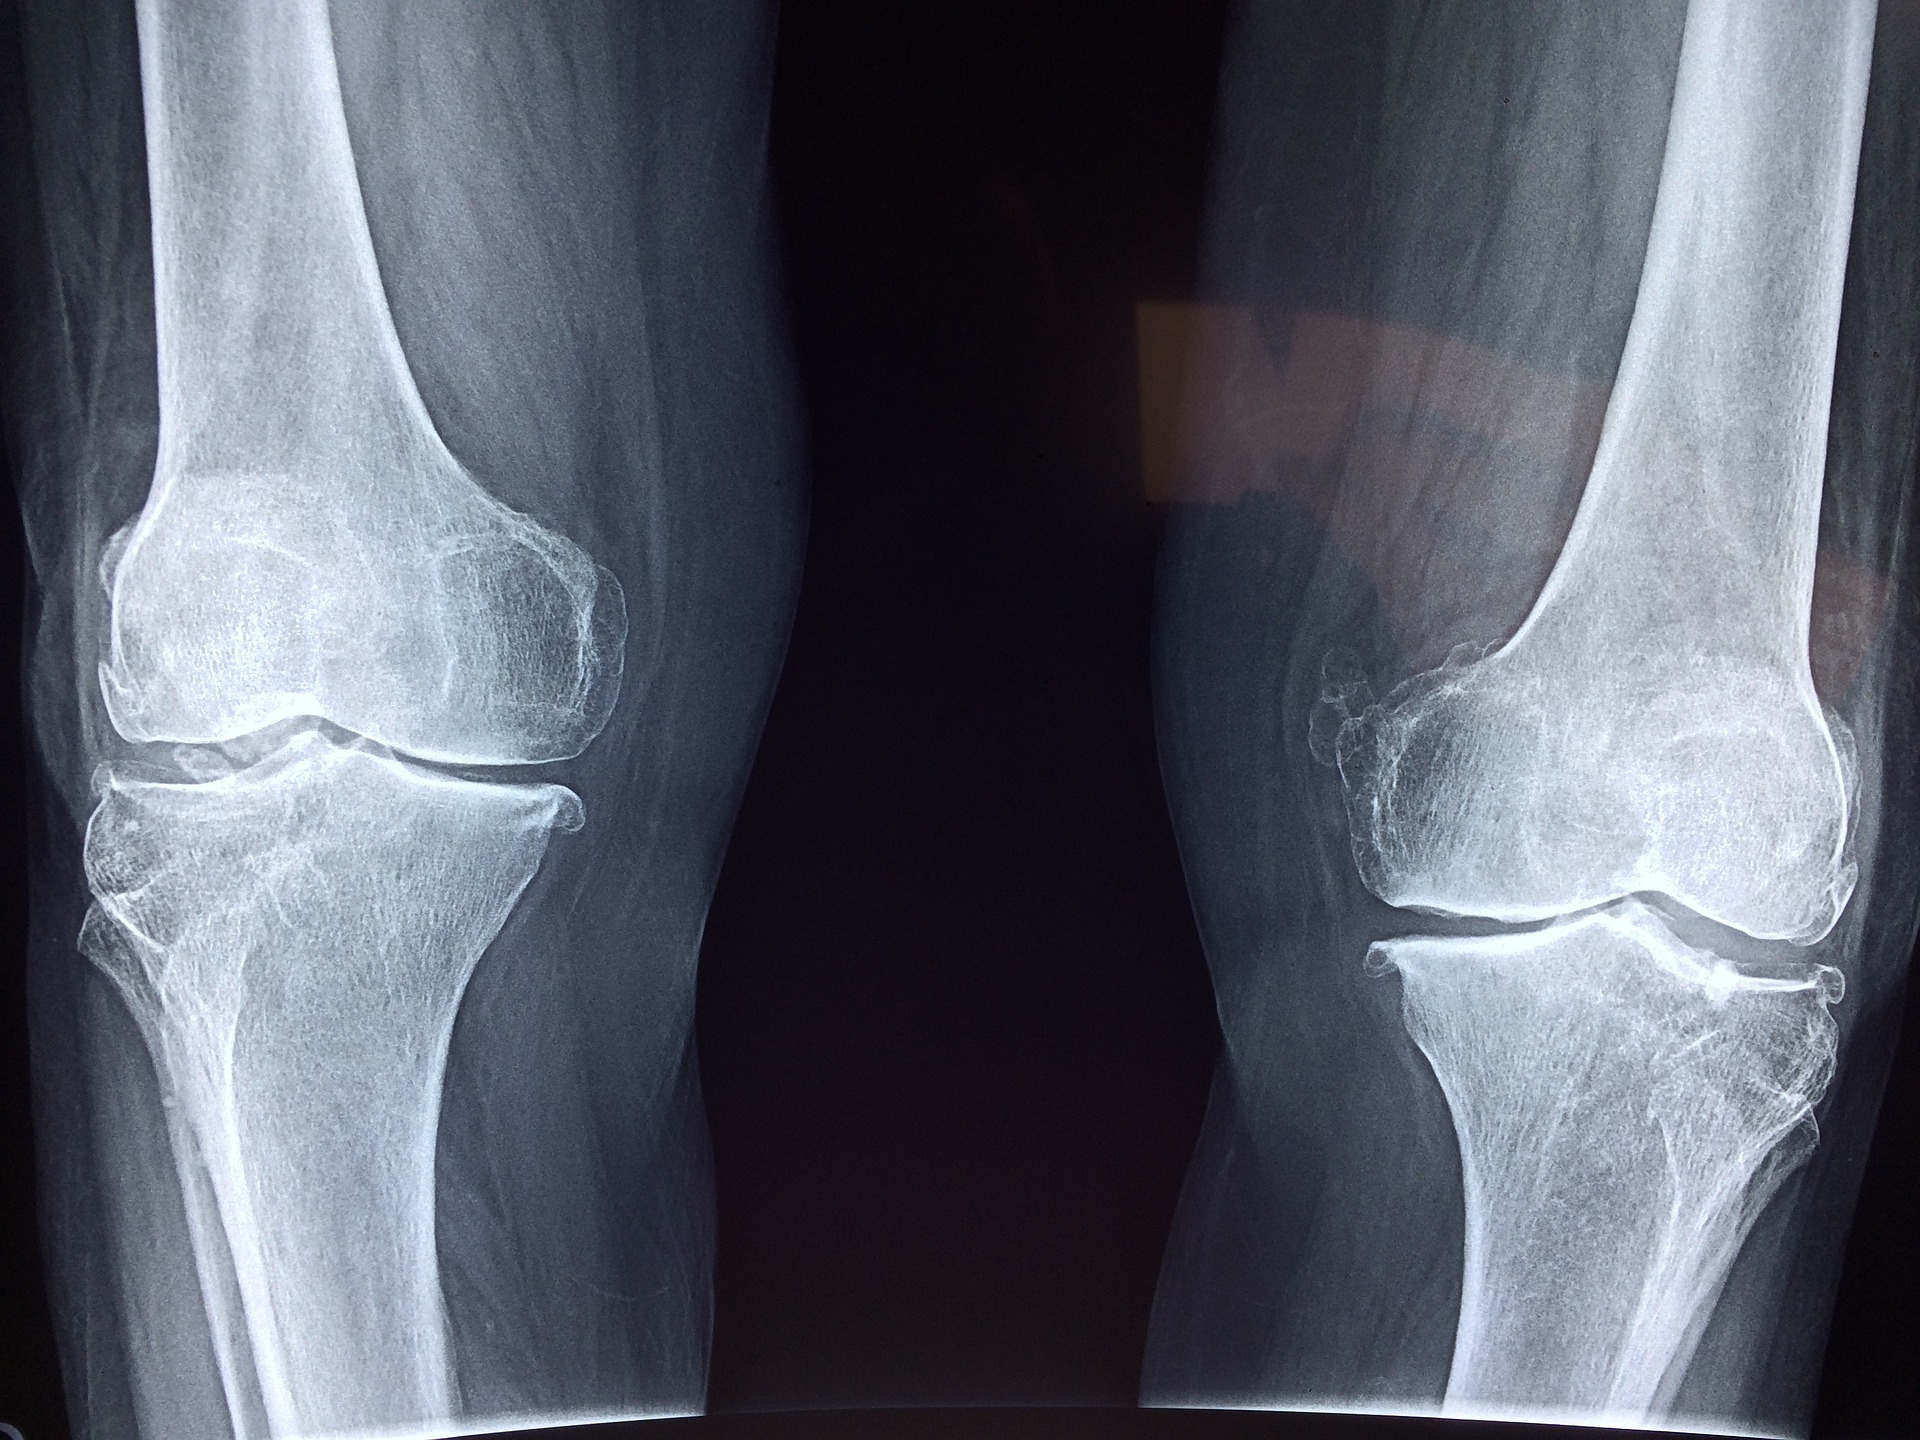

퇴행성관절염은 관절염 중 가장 흔한 형태 중 하나입니다.

관절염은 관절의 염증으로 인해 발생하는 질환으로, 퇴행성관절염은 연령과 운동의 강도에 따라서 차등적으로 발생할 수

있습니다.

퇴행성관절염은 일반적으로 손목, 손가락, 무릎, 엉덩이, 등과 같은 관절에서 발생합니다.

이러한 관절들은 연골로 덮여 있으며, 연골은 관절이 부드럽게 동작할 수 있도록 해줍니다.

그러나 퇴행성관절염은 연골의 파괴로 인해 관절이 더 이상 부드럽게 동작하지 않고, 관절 퇴행을 일으키며 관절통,

강직, 염증 등의 증상을 유발합니다.

퇴행성관절염의 원인은 여러 가지이며, 가장 흔한 원인은 연령, 유전, 비만, 관절 손상 등입니다.